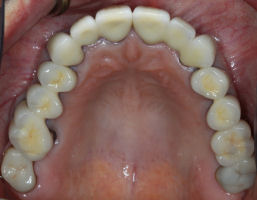

This is an advanced set of dental procedures best carried out by prosthodontists or restorative dentists. Full mouth rehabilitation is a term used in dentistry for rebuilding teeth and supporting structures after decay and gum disease has been stabilised. Full mouth rehabilitation is only required if your bite has collapsed or you have multiple missing or heavily filled teeth. Implants, crown and bridgework and/or partial or full dentures can be used to restore your bite close to its original height. Temporary restorations or dentures are used to get an idea of what the final result will be like before having the final restorations made. Temporary restorations also allow you to have input into your appearance and smile giving you the opportunity to show friends and family what your teeth may look like when the work is complete.

Before/After